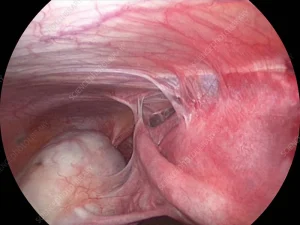

درمان اندومتریوز؛ راهنمای جامع برای انتخاب بهترین روش

درمان اندومتریوز رحم یکی از دغدغههای بیماران این بیماری است، که در بیشتر موارد این عارضه در سن باروری ایجاد میشود. که میتواند زندگی، باروری

درمان اندومتریوز رحم یکی از دغدغههای بیماران این بیماری است، که در بیشتر موارد این عارضه در سن باروری ایجاد میشود. که میتواند زندگی، باروری